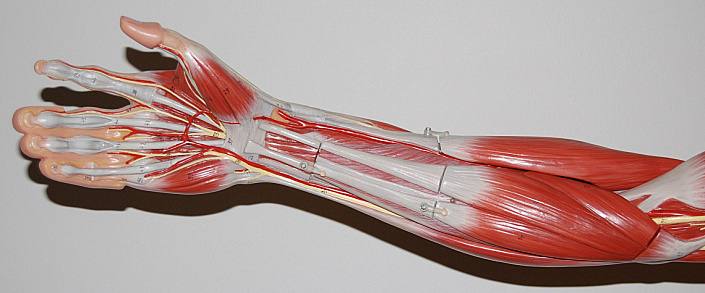

В состав ладони человека входят сухожилия, выполняющие роль сгибательных механизмов, а задняя часть руки – сухожилия, играющие роль разгибателей. При помощи этих групп сухожилий рука может сжиматься и разжиматься.

Нужно отметить, что на каждом пальце на руке так же расположено по два сухожилия, позволяющие сгибать кулак:

Строение мышц руки

Мышечный каркас рук делится на две большие группы — плечевого пояса и свободной верхней конечности.

Плечевой пояс вобрал в себя следующие мышцы:

Свободную верхнюю поверхность составляют мышцы:

На плечо приходится большая часть физической нагрузки во время выполнения работ, поэтому его мышечная система представлена сильными, прочными и мощными мышцами, которые легко поддаются физическому развитию и совершенствованию. Основная часть волокон окружает плечевую кость, располагаясь параллельно вертикальной оси. Кожа в этой области сравнительно тонкая, поэтому у физически развитых мускулистых людей места прикрепления и основные изгибы мышц заметно выделяются. Считается, что объём и рельефность предплечья прямо пропорциональна силе человека, но это не совсем корректно: основой физической силы служат не размеры мышц, а их натренированность, способность быстро сокращаться и расслабляться при воздействии высоких нагрузок.

Функции плеча разнообразны и включают практически полный спектр движений руки. Чтобы понять, как функционирует эта система, давайте рассмотрим анатомию ключевых мышц, за счёт которых осуществляются те или иные действия.

Бицепс

Бицепсом называют двуглавую мышцу плеча, обе головки которой плотно охватывают верхнюю часть плечевой кости. Две головки бицепса — короткая и длинная — начинаются в районе плечевого сустава, а примерно в середине плечевой кости переплетаются воедино, спускаясь к круглому возвышению на предплечье.

Благодаря сокращению и расслаблению мышечных волокон, образующих бицепс, человек может выполнять следующие действия:

Трицепс

Трицепс, или трёхглавая мышца плеча, состоит из трёх головок различной длины, которые охватывают локтевой и частично плечевой суставы с задней стороны руки. Медиальная и латеральная веретенообразные головки трицепса берут начало в районе плечевой кости, а длинная закрепляется на выступе лопатки. Они так же, как и головки бицепса, сливаются в одну систему в нижней части плеча, образуя сухожилие, прикреплённое к локтевому отростку кости предплечья.

Функции трицепса заключаются в следующем:

Плечевая мышца

Эта мышца располагается непосредственно под бицепсом и выходит на поверхность мышечного скелета только в месте прикрепления в нижнем сегменте плечевой кости. Она не настолько мощная по сравнению с бицепсом, однако также играет ключевую роль в физиологических возможностях руки — благодаря её ритмичным сокращениям человек может поднимать локтевую кость и сгибать предплечье.

Плечелучевая мышца

Как видно из названия, эта группа мышечных волокон соединяет плечевой и локтевой суставы, располагаясь вдоль всей длины плечевой кости. Главной её функцией является сгибание руки в локте при сокращении. Заметить эту мышцу можно на поверхности локтевой ямки — особенно выраженно её хребет выступает при поднятии тяжестей.

Мышцы предплечья делятся на 3 ключевые группы. Спереди располагаются волокна, которые контролируют сгибание и разгибание запястья и пальцев, сзади — мышцы-разгибатели, а сбоку — группа, отвечающая за движение противопоставленного большого пальца.